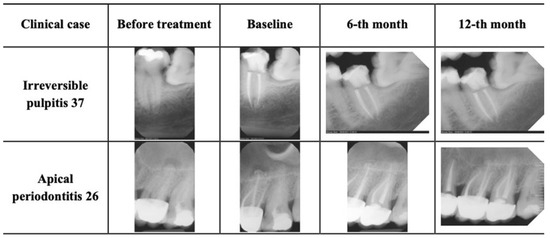

Clinical and Radiographic Outcomes of Root Canal Obturation with Hydraulic Condensation and Tricalcium Silicate Bioceramic Sealer: A 12-Month Observational Study on Periapical Healing

Successful endodontic treatment relies on effective shaping, disinfection and obturation. Calcium silicate sealers such as BioRoot™ RCS show promise due to their bioactivity and sealing properties, but more clinical evidence using standardized protocols is needed. This observational clinical study aimed to assess periapical [...] Read more.

Successful endodontic treatment relies on effective shaping, disinfection and obturation. Calcium silicate sealers such as BioRoot™ RCS show promise due to their bioactivity and sealing properties, but more clinical evidence using standardized protocols is needed. This observational clinical study aimed to assess periapical healing at 6 and 12 months following single-visit root canal treatment using BioRoot™ RCS with hydraulic condensation in teeth with irreversible pulpitis or apical periodontitis. Sixty-six teeth were treated using a standardized protocol: ProTaper Gold instrumentation, sonic-activated irrigation, and hydraulic condensation with gutta-percha cone and BioRoot™ RCS. Periapical healing was evaluated using the periapical index (PAI) at baseline, 6 months, and 12 months. Clinical success was defined as functional, asymptomatic teeth and a PAI ≤ 2. Statistical analysis included repeated measures of ANOVA and McNemar’s test. All 66 teeth remained asymptomatic and functional of 12 months, yielding a 100% survival rate. Clinical success was confirmed in 97% of cases. PAI scores decreased significantly over time (p < 0.001) in apical periodontitis cases. Single-visit endodontic treatment with BioRoot™ RCS and hydraulic condensation demonstrated excellent clinical and radiographic outcomes. This approach promotes resolution of apical periodontitis in non-vital cases and supports the preservation of periapical health in teeth initially diagnosed with irreversible pulpitis. Full article